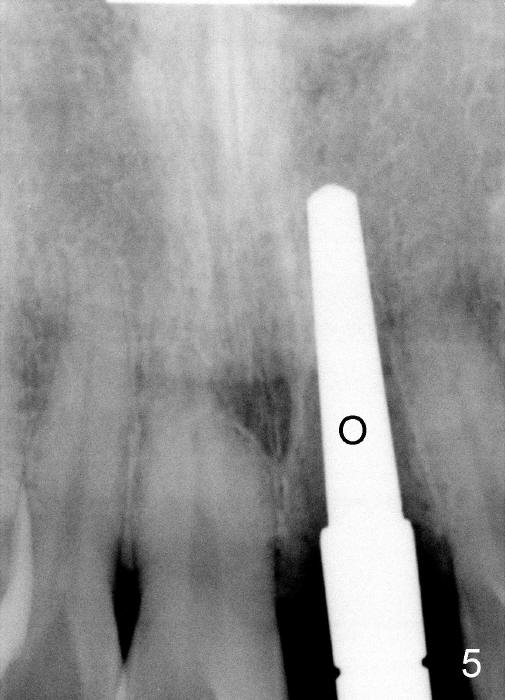

The upper right central incisor (Fig.1: #9) fractures subgingivally due to trauma for a 40-year-old man.  The incisive canal is large (I) and close to the root of the central incisor.  After extraction, the osteotomy (Fig.3b, 4: O) is made with 2 mm pilot drill (Fig.2: D) on the lingual wall (Fig.3a: L) of the socket (Fig.3a: S).  To push the incisive canal mesially, the osteotomy is enlarged by 3.5x21 mm and 4x21 mm tapered osteotomes (Fig.5,6: O).  Due to the lingual slope (Fig.7a arrow), the osteotome (blue outline) starts to deviate bucally.  To reduce this tendency, the coronal portion of the lingual slope is removed (Fig.7b: yellow circle).  The final implant (4.5x20 mm) is able to be placed as lingually as possible (Fig.7c, 8).